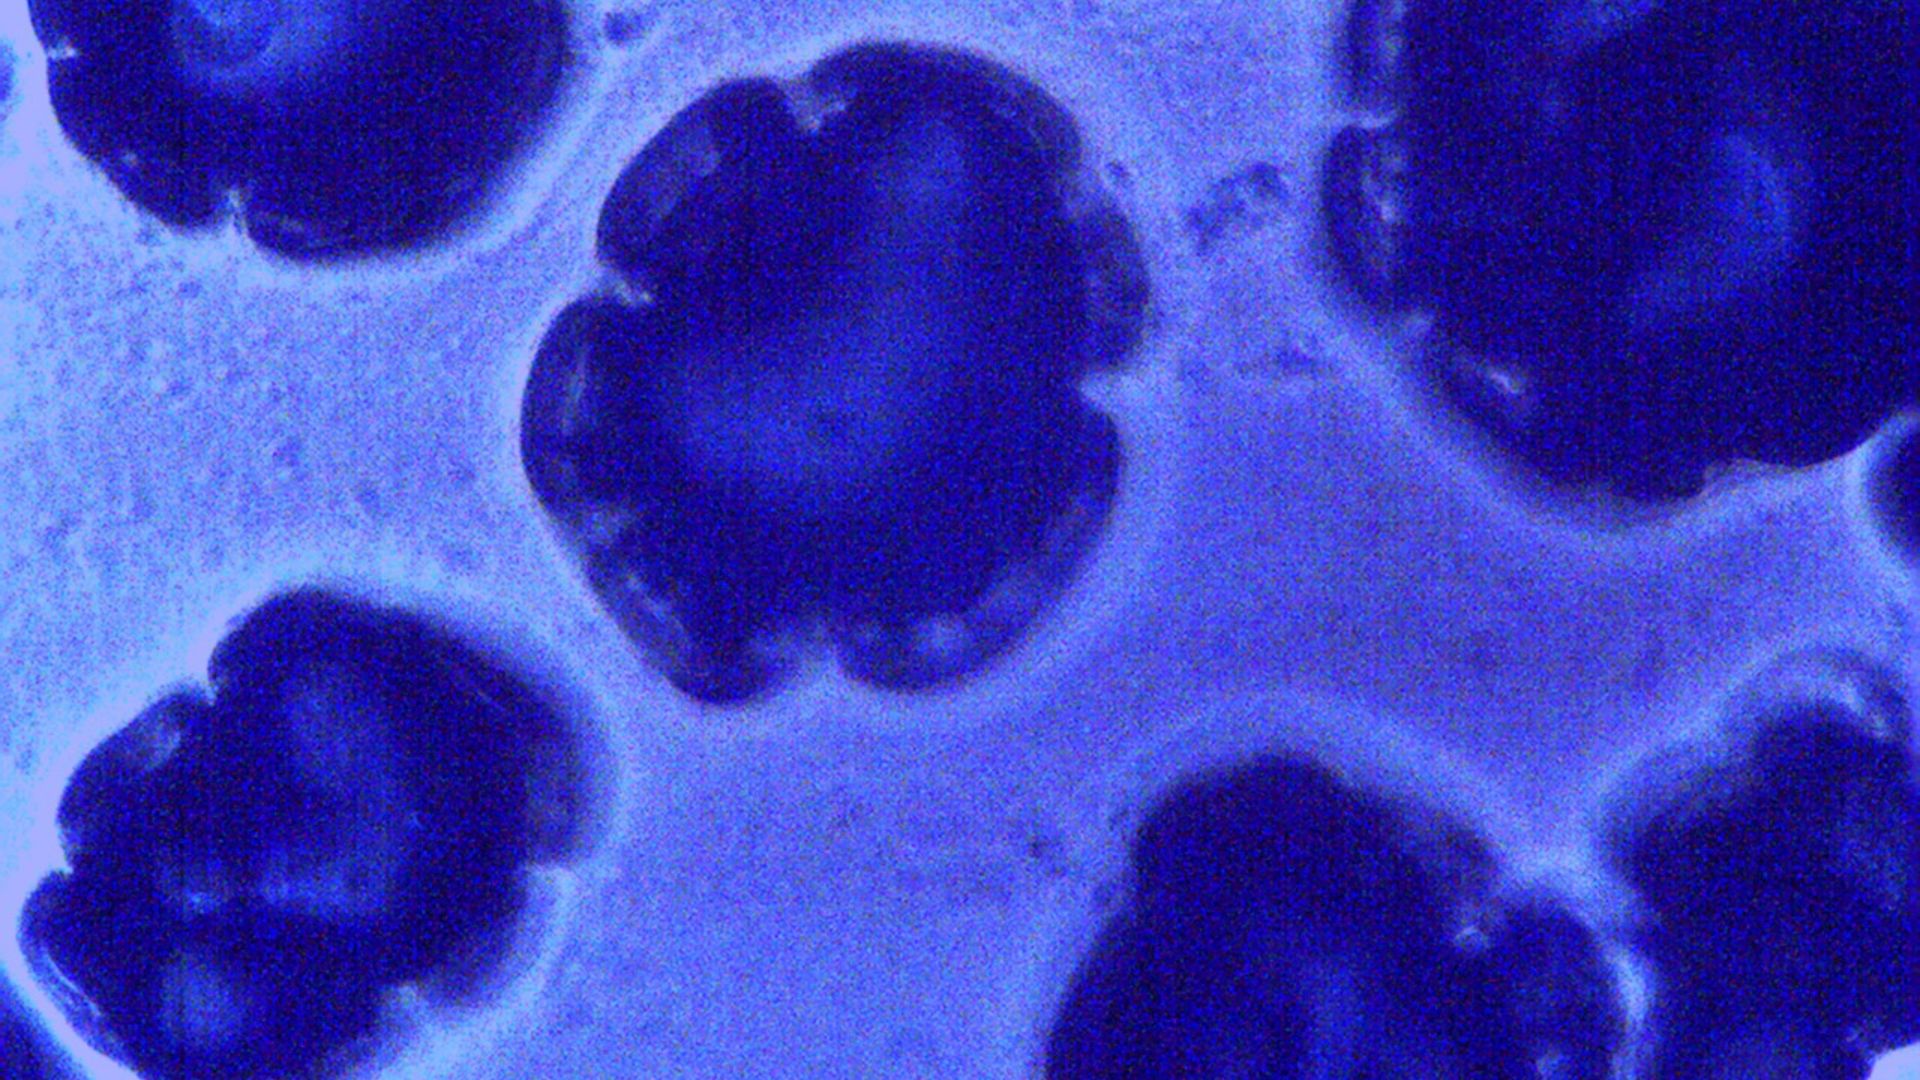

2. Bifidobacterium longum

This strain helps calm inflammation, support your immune system, and even lift your mood, proving that the gut-mind connection is real. You’ll often see it in fermented dairy and “mood” probiotic blends.

5. Bifidobacterium bifidum

This is one of the first strains to colonize your intestines after birth. Later in life, it reliably helps digest dairy, supports your immune system, and can make you less susceptible to colds.

7. Bifidobacterium breve

This strain is especially beneficial for babies and assists in breaking down sugars in breast milk as well as reducing their eczema risk. That said, adults benefit too, especially when it comes to bloating and IBS.